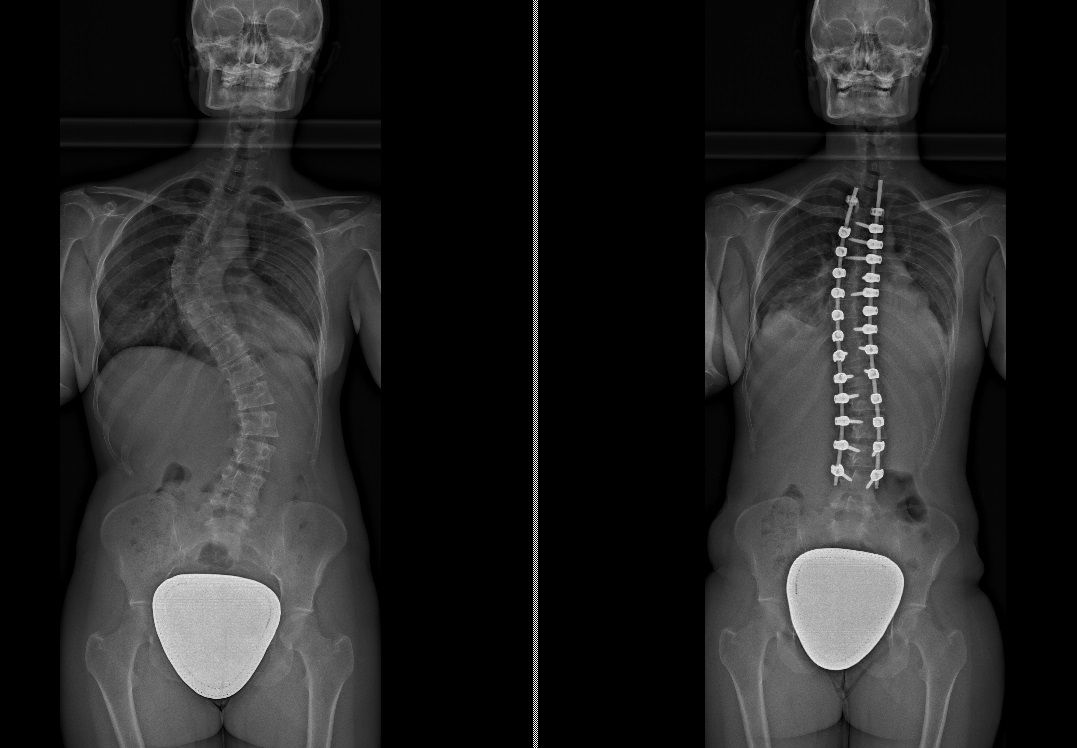

Laureato in Medicina e Chirurgia presso l'Università degli Studi di Napoli Federico II nel 2011, Specializzato in Ortopedia e Traumatologia presso la stessa Università nel 2017. Da subito ho dedicato i miei studi all'ambito della chirurgia vertebrale e della neurochirurgia. Infatti ho frequentato per 9 mesi tra il 2015 ed il 2016 i reparti di Neurochirurgia dell'IRCCS Neuromed di Pozzilli (IS) per apprendere le tecniche di trattamento delle Patologie della Colonna Vertebrale. Da allora il mio principale interesse è rivolto al trattamento conservativo e, dove necessario, chirurgico delle deformità della colonna vertebrale, sia dell’età dell’accrescimento che degenerative dell’adulto: scoliosi, dorso curvo, spondilolisi, spondilolistesi. Ulteriori campi di interesse sono il trattamento di lombalgia e lombosciatalgia, ernia del disco, stenosi del canale vertebrale, fratture vertebrali traumatiche o da osteoporosi (vertebroplastica), terapia del dolore osteoarticolare mediante tecniche mininvasive (radiofrequenze). Dal 2017 sono Consulente presso IRCCS Neuromed di Pozzilli (IS) con incarico di Responsabile del Centro per la Diagnosi e Cura delle Deformità Vertebrali e Scoliosi, dove svolgo la mia attività chirurgica in regime di convenzione. Svolgo la mia attività chirurgica in regime di solvenza e di convenzione assicurati presso la Clinica Ruesch di Napoli. Continuo costantemente la mia formazione con esperienze di perfezionamento nazionali ed internazionali. Infine, dal 2020 sono Docente per l'Università degli Studi di Roma "La Sapienza".

Foto e video